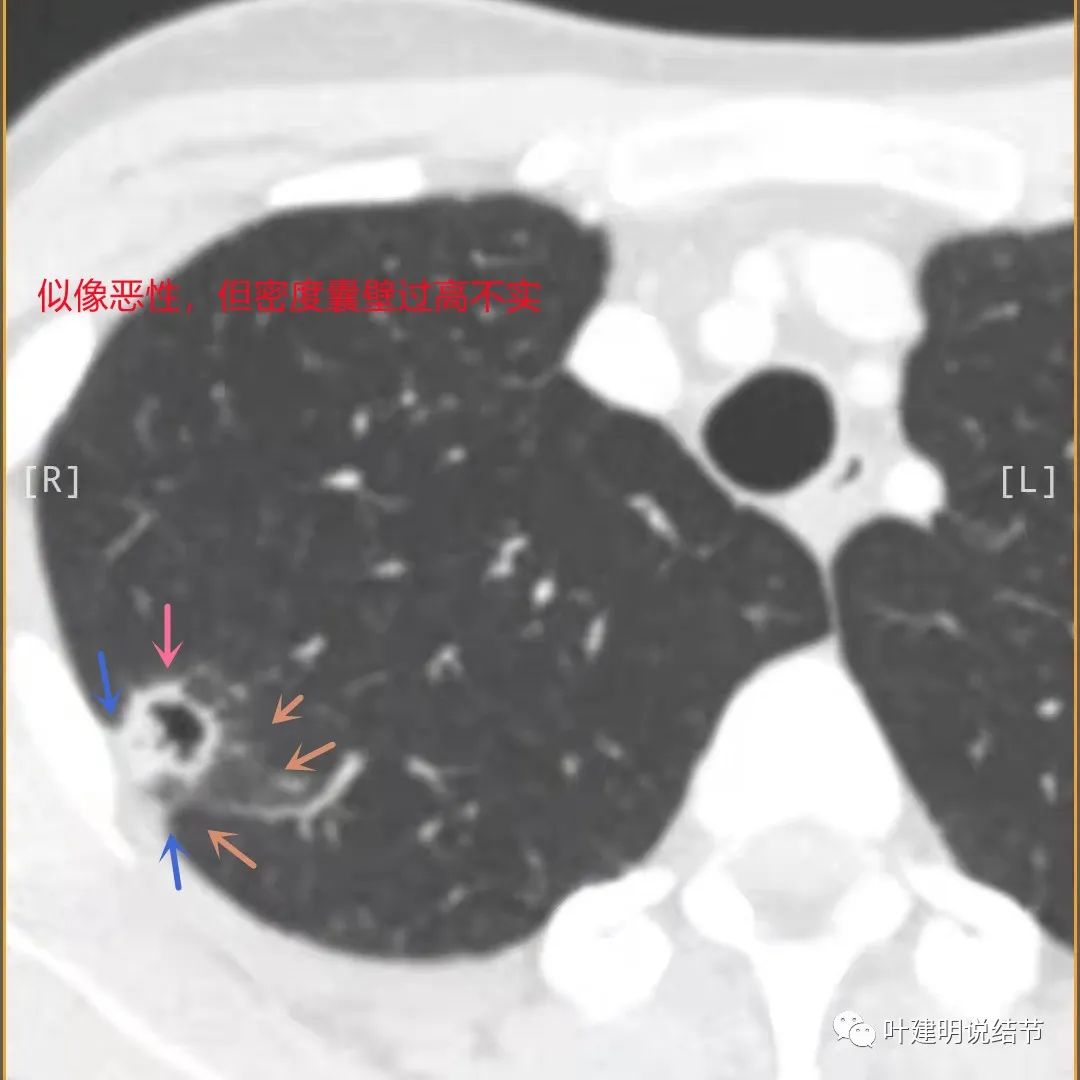

上图也像恶性,但整个囊壁的密度感觉过高了点,边缘磨玻璃淡、散且模糊,邻近胸膜有增厚

邻近胸膜有增厚(蓝色箭头),主病灶的壁密度过高且整个壁密度都高(粉色箭头),旁边有磨玻璃影,散且模糊(砖色箭头)。内壁不均质(此不舒服)

邻近胸膜有增厚(蓝色箭头),主病灶囊壁密度过高(粉色箭头),内部有突起(细红色箭头),旁边有磨玻璃影,散且模糊(砖色箭头),中间有空腔,内壁有些区域又是光滑的

病灶有明显强化(说明炎性可能性大,如果恶性这样强化,血供丰富,应该倍增速度更快。蓝色箭头示胸膜处低于软组织密度的区域;桔色箭头示病灶边缘平直缺乏膨胀性;黄色箭头示中间的空腔

薄层影像印象:病灶有明显强化,且邻近胸膜处及部分囊壁区有极低密度区域,考虑干酪样坏死可能性大,肿瘤的坏死可能性小,肿瘤一般要长的比较大,中央缺血性坏死。整体病灶也是觉得散,且邻近胸膜处甚厚。考虑炎性,尤其是肉芽肿性炎伴干酪样坏死可能性大。